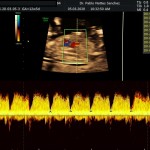

- La vitalidad fetal (Doppler fetal).

- El Doppler de las arterias uterinas maternas y determinación de riesgo y prevención para pre eclampsia severa.